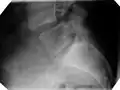

![]() | |

| X-ray of the lateral lumbar spine with a grade III anterolisthesis at the L5-S1 level. | |